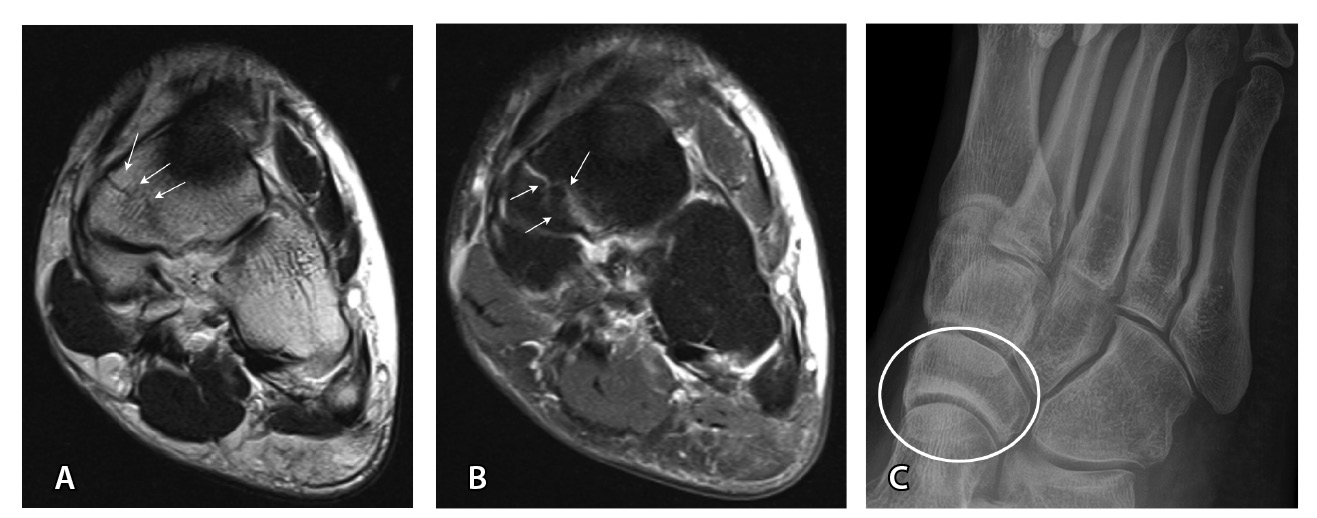

Переломы без смещения фрагментов, а также краевые и авульсионные переломы не всегда четко визуализируются на рентгенограммах из-за суперпозиции теней, наличия фиксирующих шин и гипсовых повязок, которые накладываются на зону интереса. При клинических признаках перелома и рентгеннегативной картине у таких пациентов КТ имеет большую диагностическую значимость (рис. 2).

Рис. 2. Рентгеннегативный перелом дистального метадиафиза большеберцовой кости 2-го типа по Солтеру – Харрису (стрелки) у мальчика 11 лет: А, Б – рентгенография; В – компьютерная томография (КТ), корональная плоскость; Г – КТ, сагиттальная плоскость; Д – КТ, аксиальная плоскость